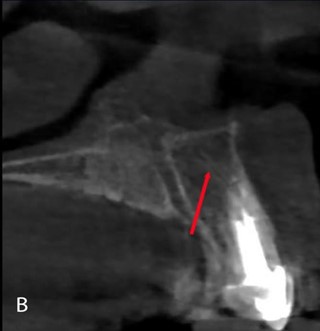

Затем мы оценили 149 визуализированных КС по их расположению в альвеолярном отростке. Установлено, что 76% КС имели нёбную локализацию, а у 12% – как центральную, так и вестибулярную (рис. 4, а, б, в). Эти данные представлены в таблице 3.

Рисунок 4. Визуализация КС в зависимости от локализации: а – небная локализация; б – центральная и в – щечная локализация.